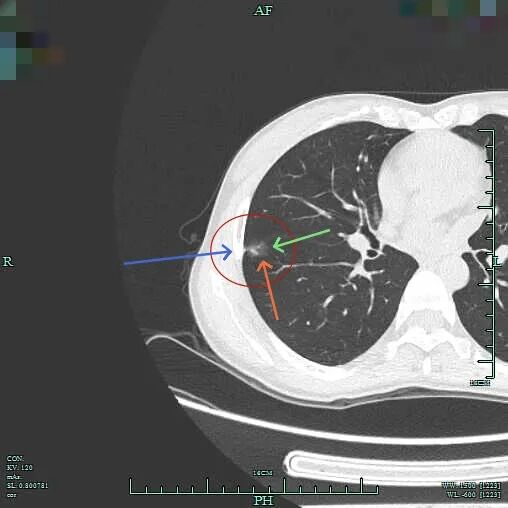

上图层面密度较淡,表面不平,有微小血管进入。

边缘区较淡,边也不光滑。

靶重建影像示混合密度,表面不平。

灶内偏实性成分明显,但不是太高的密度,贴胸膜近,略有牵拉,浅分叶明显,整体轮廓与瘤肺边界清。

病灶表面不平,灶内密度欠均,邻近胸膜略牵拉。

密度不均,轮廓较清,灶内有明显偏实性成分。